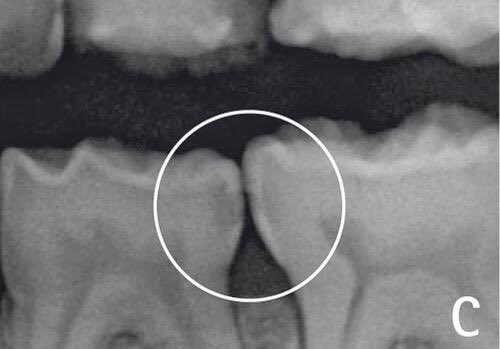

يحدث التسوس بين الأسنان بسبب تراكم بقايا الأكل في الفراغات الموجودة بين الأسنان ، وصعوبة وصول فرشة الأسنان للمكان، وفي الغالب يكون غير مرئي يعني سطح السن العلوي يكون سليم لكن التسوس من جانب السن.

طريقة تجنبها سهلة جداً، في المقام الأول: الزيارة الدورية للطبيب مهمه وهي اللي تكشف هذه التسوسات بعد أخذ صور الأشعة والكشف السريري ويتم معالجتها قبل ماتتعمق وتوصل لعصب السن.